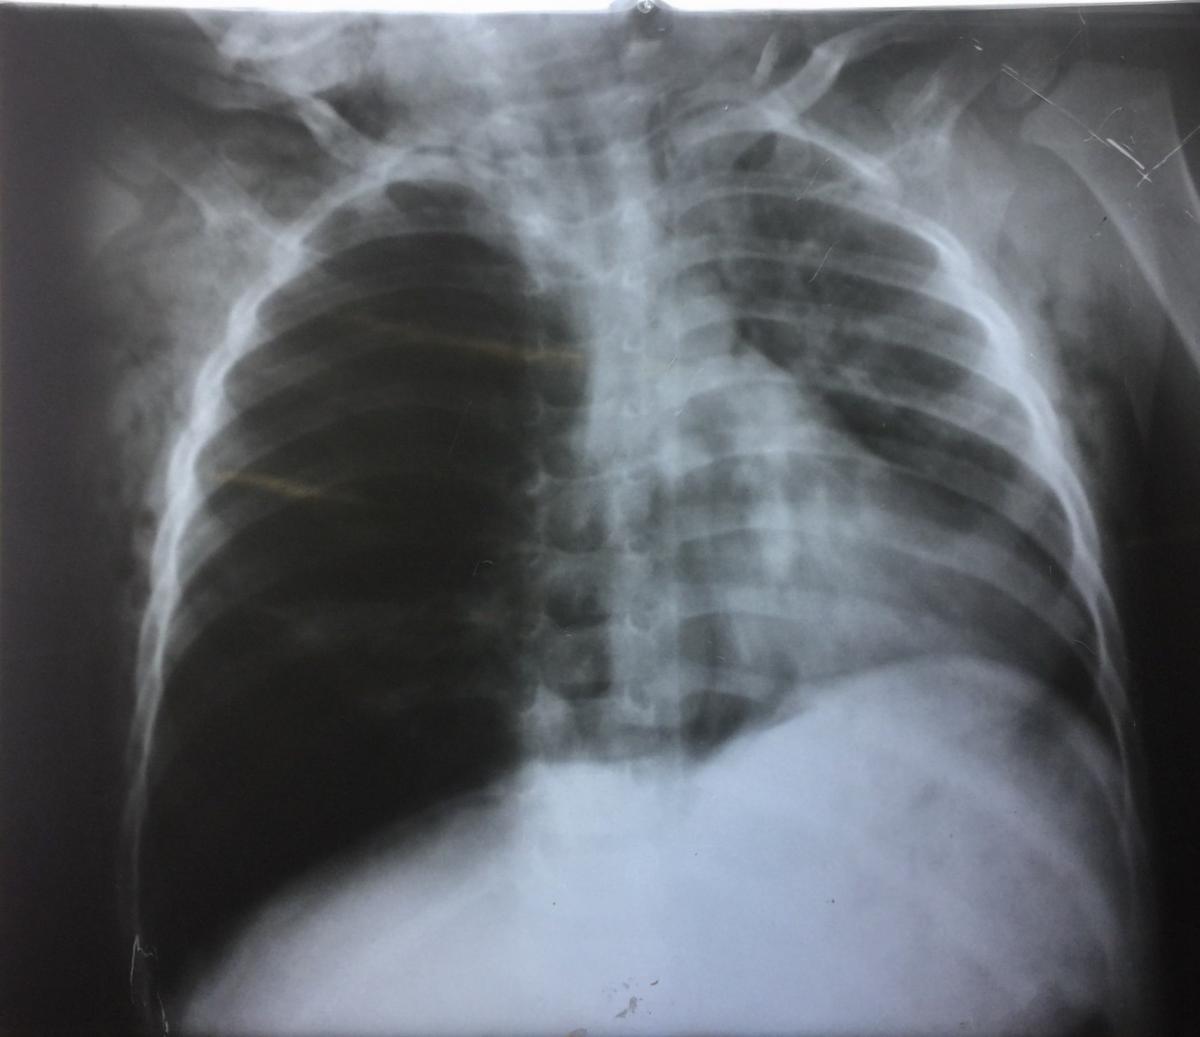

A chest x-ray (Figure 1) and computed tomography scan of the chest (Figure 2) revealed hyperinflation of the right lung, subcutaneous emphysema, and pneumomediastinum.